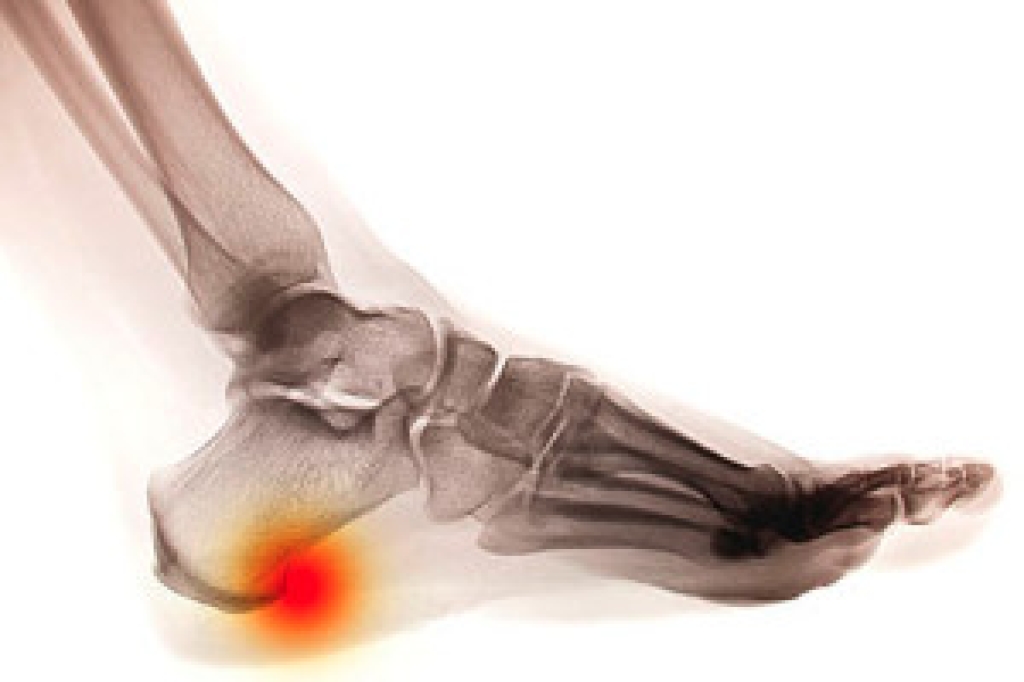

Diabetes affects millions of people every year. The condition can damage blood vessels in many parts of the body, especially the feet. Because of this, taking care of your feet is essential if you have diabetes, and having a podiatrist help monitor your foot health is highly recommended.